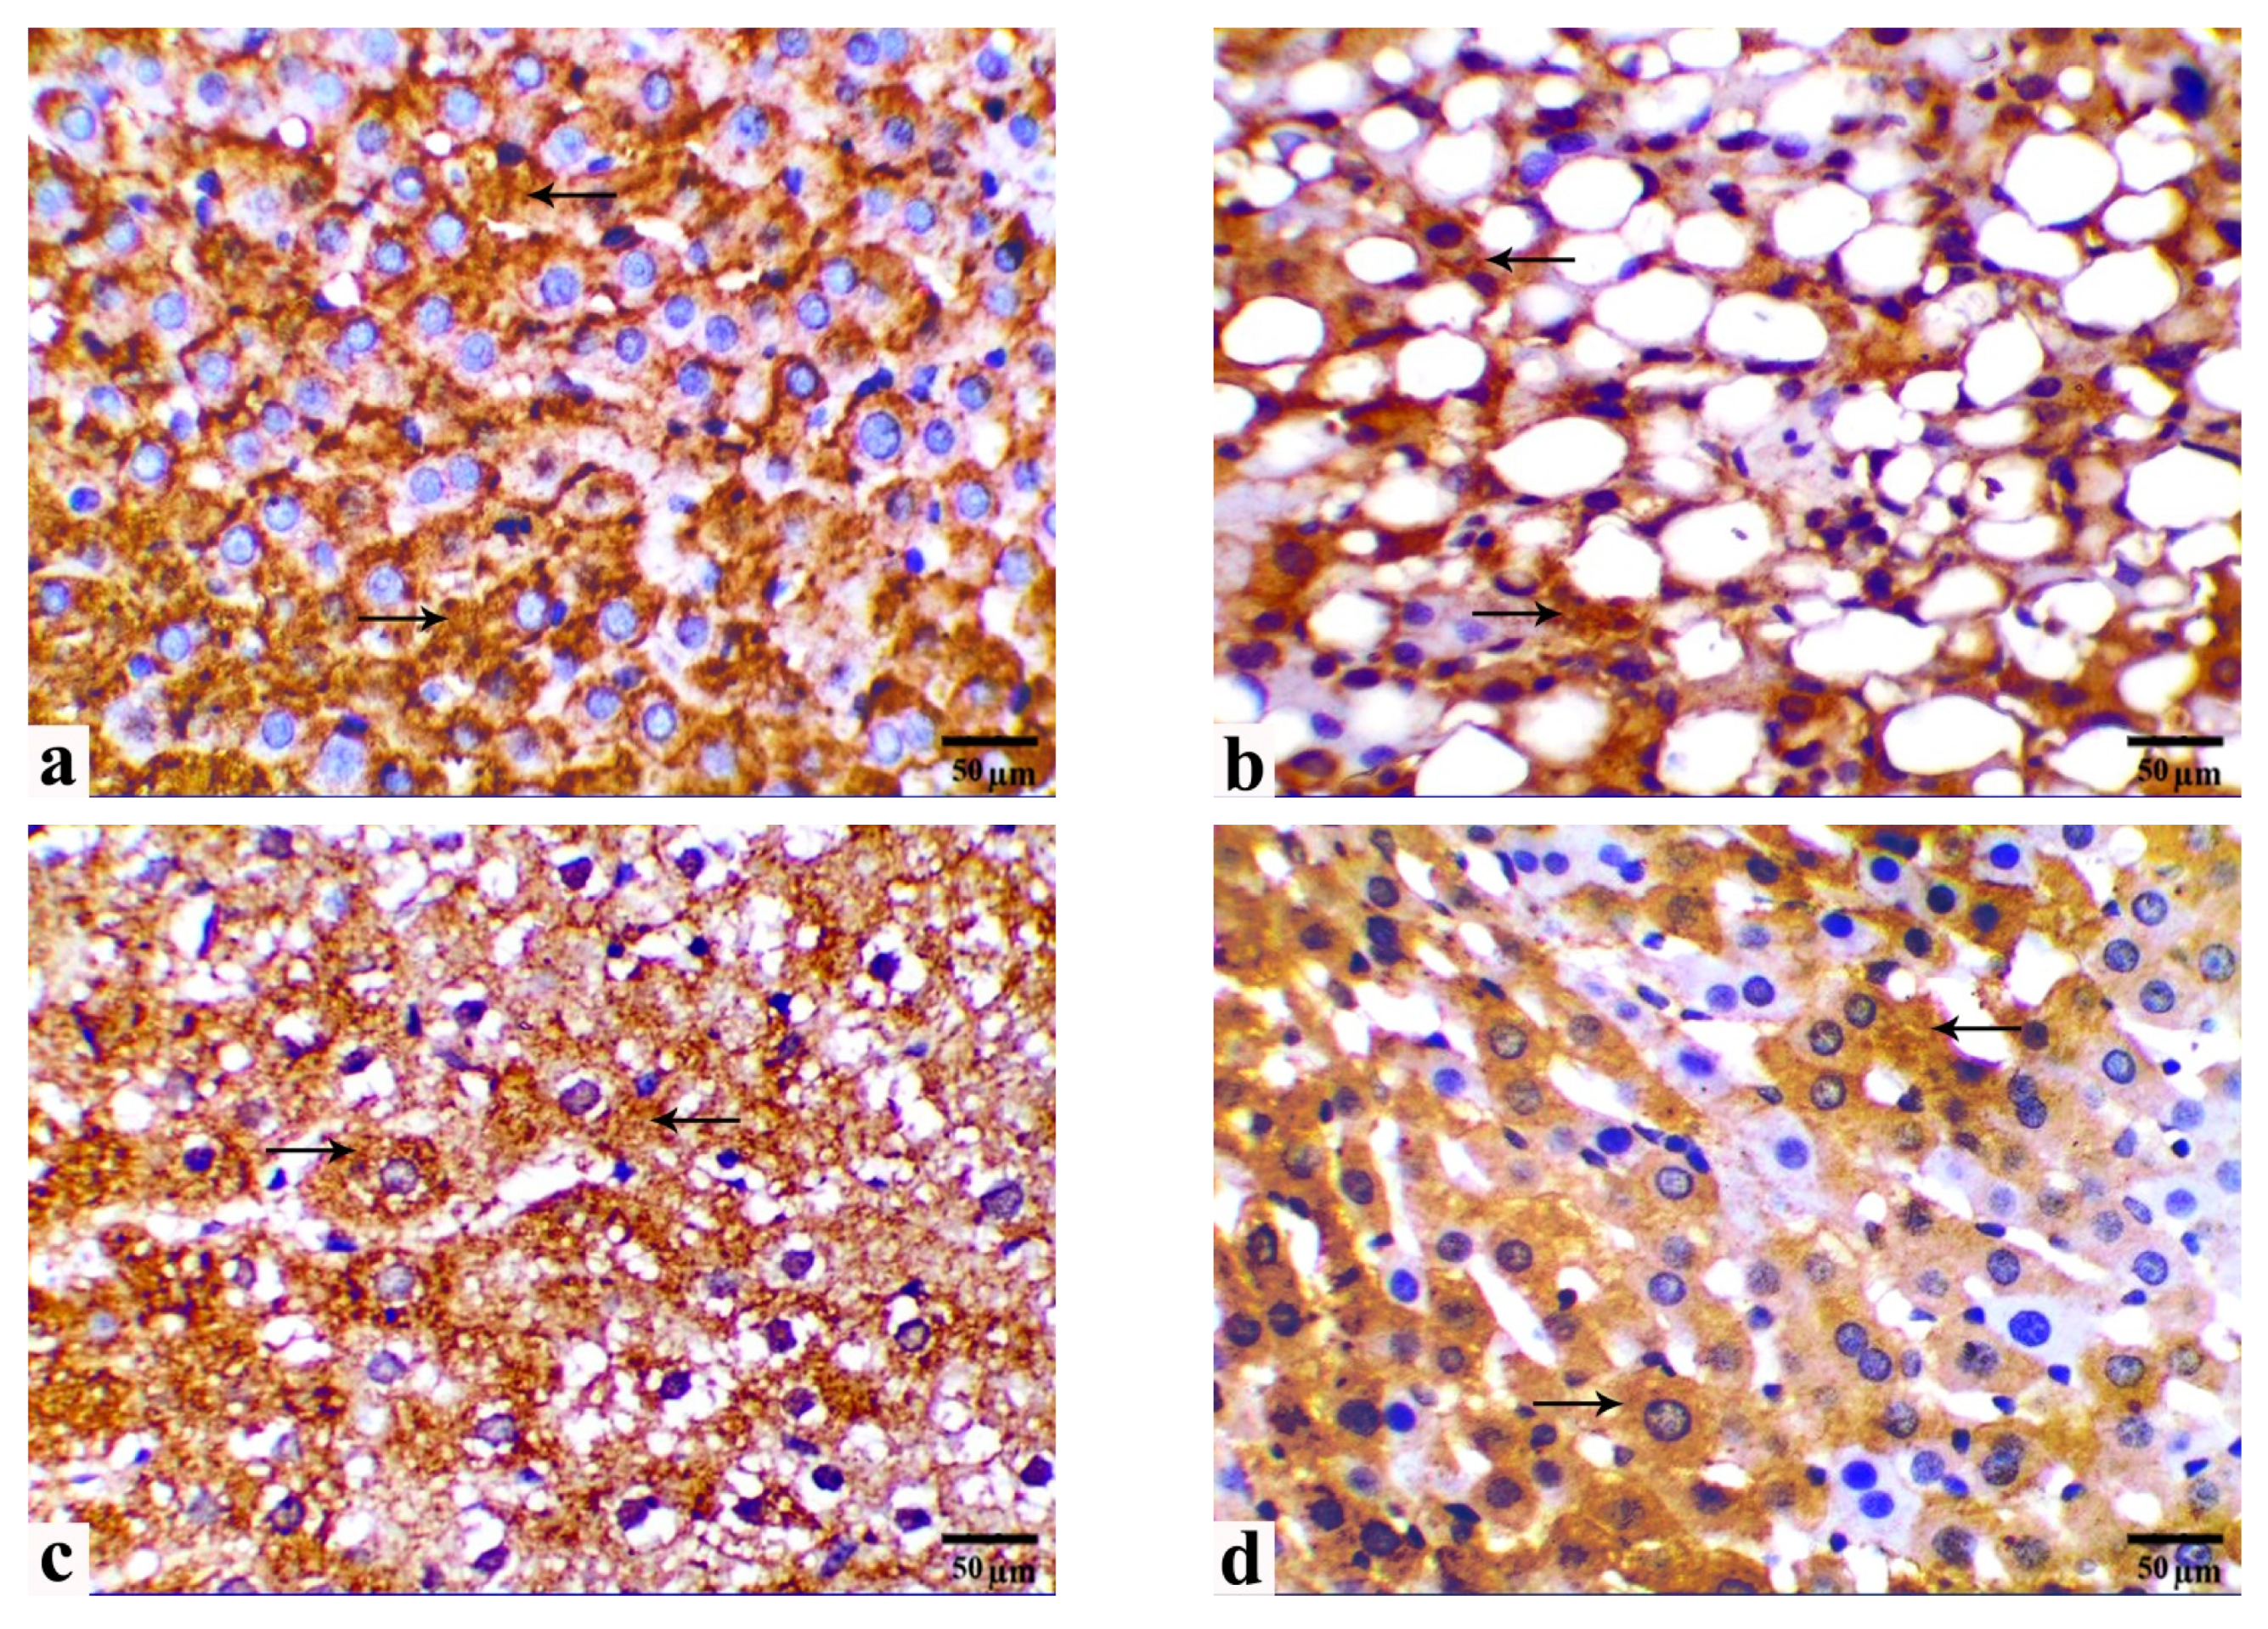

3.5. Immunohistochemical Observations